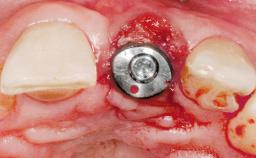

Immediate Placement of an Implant in a Maxillary Right Central Incisor Site

A 30-year-old female patient was referred to the office for the treatment of tooth 11. Her chief concern at the initial visit was to inquire, “Why is my tooth pink?” Upon clinical examination, it was determined that tooth 11 had a previous history of trauma and that the clinical crown had become noticeably pink in color as a result of internal resorption. This diagnosis was confirmed radiographically, indicating a large radiolucency involving the central and distal portions of the clinical crown. It was determined that restoration of this tooth was not possible, and that extraction was indicated. The presence of a mid-line diastema, which the patient wanted to reproduce, directed the treatment plan for tooth replacement utilizing a dental implant.

Bone Augmentation Horizontal|Simultaneous

Augmentation Materials Autogenous chips|Membrane

Socket Integrity Sufficient, with intact bone walls

Bone Volume Sufficient, with intact walls